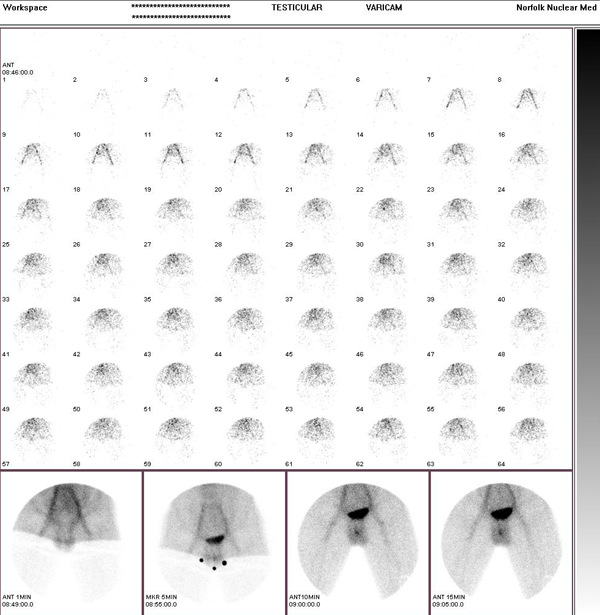

Testicular Scan